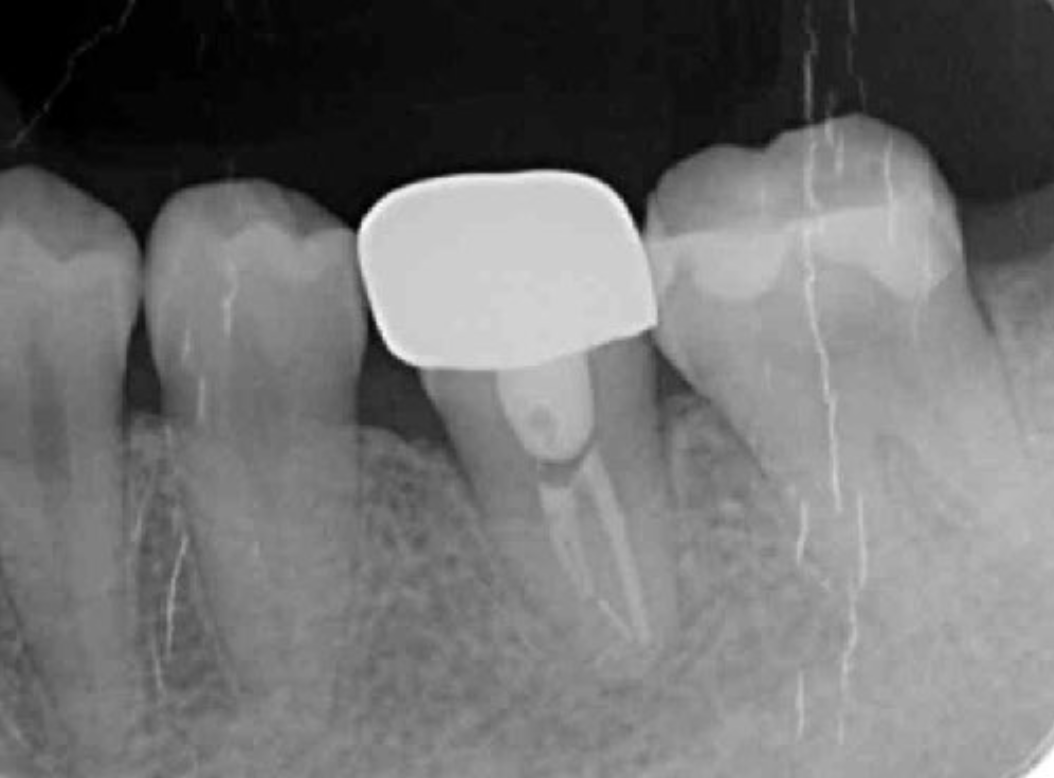

Following the operation, root canal treatment was performed as noted above. Functions including temporary crown occlusal contact and tooth mobility, as well as pocket depth were also checked. All examination results clearly indicated placement of a definitive prosthesis in the patient (Figure 13, Figure 14). At a follow-up examination one year after surgery, progress in this case was determined to be good (Figure 15).

Figure 13.Dental X-ray image obtained after confirmation of definitive prosthesis. Bone regeneration can be seen around the root of the donor tooth.